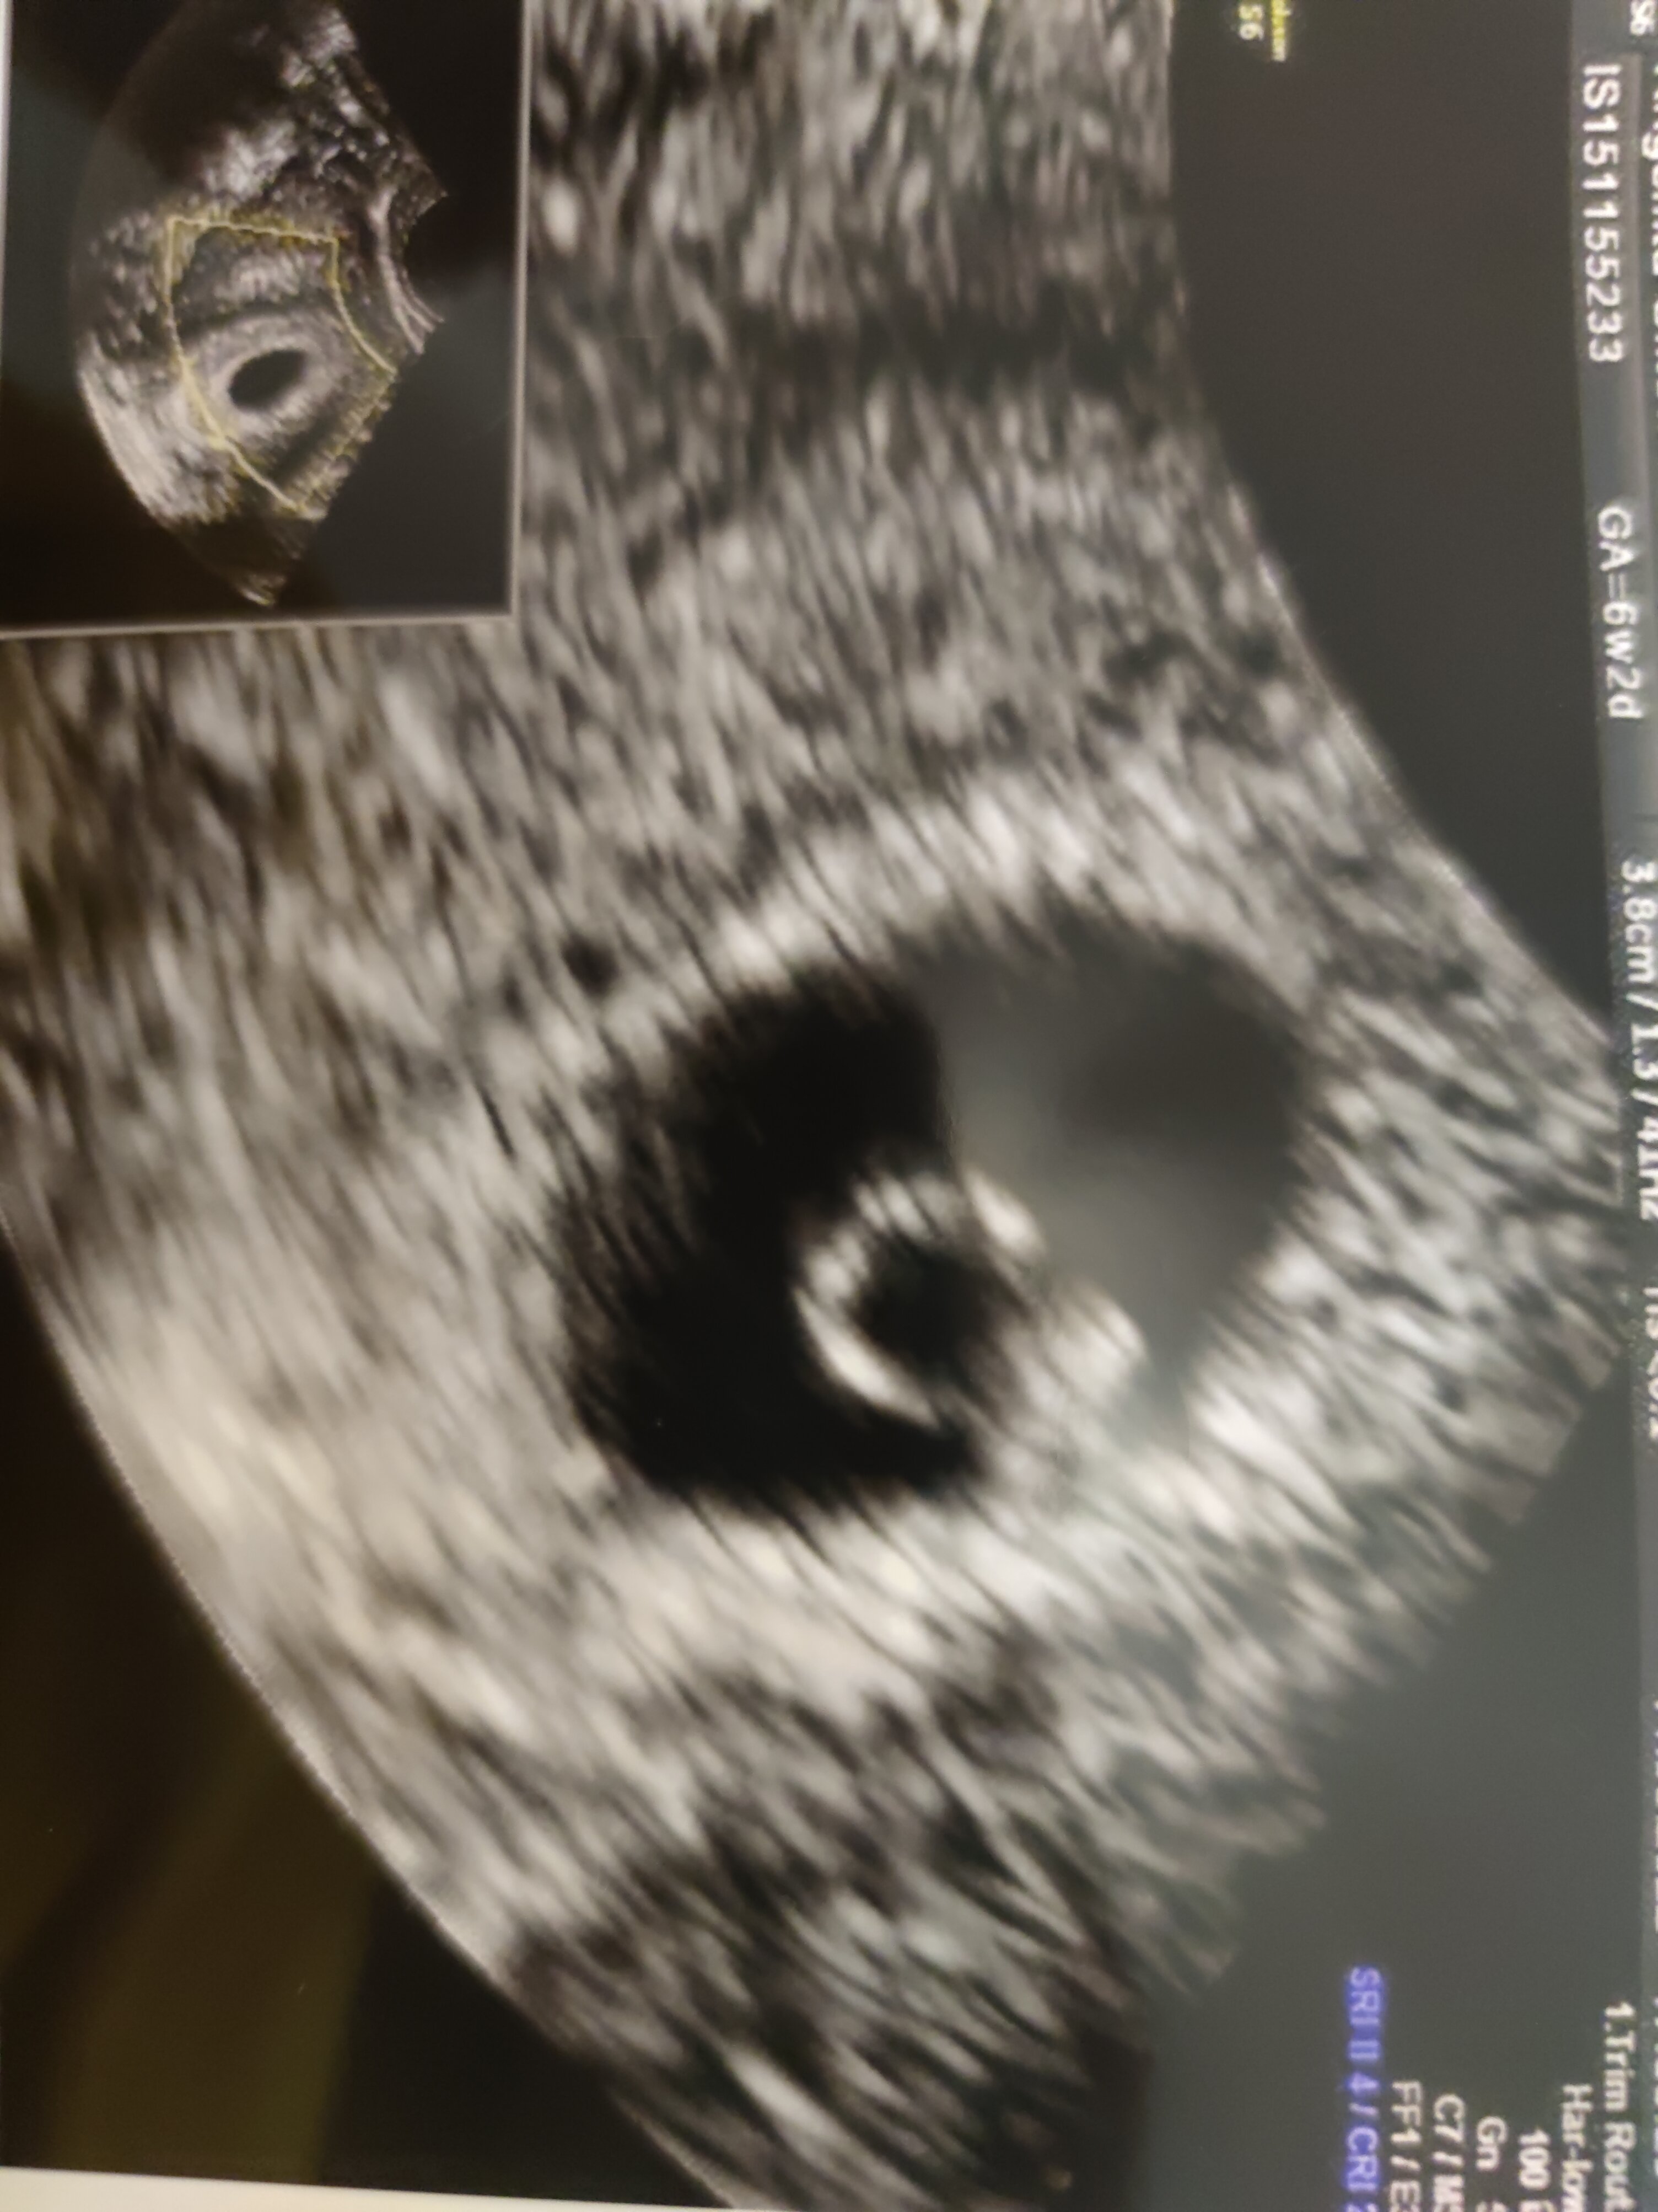

Byłam u ginekologa. Z ciążą jest w porządku, póki co. Gorzej ze mną. Ważę aktualnie 43 kilo.

Próbowałam się z nim wczoraj skontaktować ale nie odebrał ode mnie telefonu. Na innych komunikatorach zostałam prawdopodobnie zablokowana. Chciałam mu wysłać zdjęcie USG.